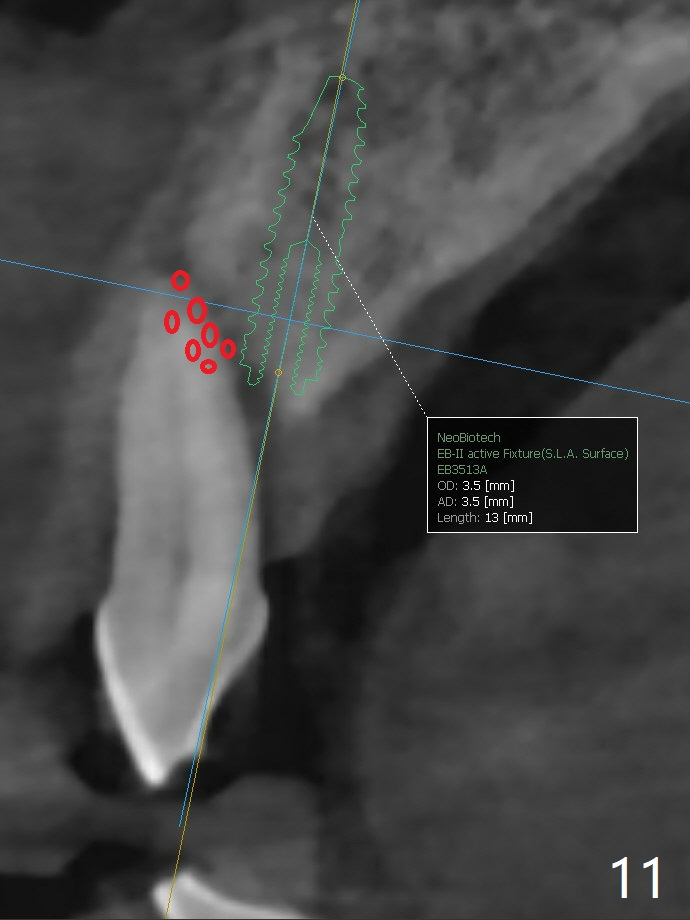

A 67-year-old man requests extraction of the loose tooth #9 (Fig.1). After extraction, the labial plate is found to be missing. With incision, allograft is kept in place with a 12x24 mm anterior narrow Cytoplast and 4-0 Chromic gut suture (Fig.2). Periodontal dressing dislodges in 2 days. The wound dehisces transversely 5 days postop (Fig.3 arrows), whereas the wound was open buccopalatal when the sutures were placed. Probably due to extensive dissection, the erythematous mucosa is large (Fig.4), although asymptomatic. When X-ray shows V-shaped bony defect (Fig.1 (PA), 5 (Pan), 6 (CT)), do not dissect the overlying thin buccal gingiva, which is most likely to dehisce. In fact immediate implant with guide appears to be more conservative, since there is no pressure against the buccal gingiva (Fig.7,8). To be more ideally, the implant could be placed more coronally, longer (13 mm instead of 11.5, Fig.9,10) and narrower (3.5 mm instead of 4.0 mm, Fig.11 (red circles: bone graft)).